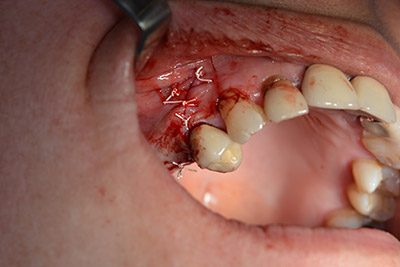

The implant was then placed and the bone built up. In this case, because of the size of the augmentation region, autologous bone chips, harvested with an osseous trap as drilling chips from implantation 16 and fenestration 14, were mixed with bone replacement material.

An absorbable membrane was used as the barrier in the buccal direction and covered the augmentation. Finally, saliva-proof sutures were placed (Fig. 15 to 19).